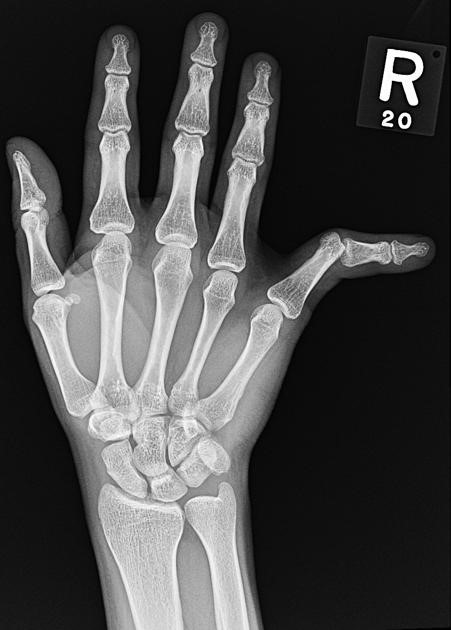

Classification of PIP joint injuries

PIP joint dislocations are classified according to the direction of the dislocation. The most common is dorsal dislocation.

There can be a volar plate avulsion +/- bone fragment. This is the big ligament on the front of the joint The collateral ligaments (ligaments on the side of the joint) are usually intact

The next most common are lateral/dorsolateral

There is usually a tear of the collateral ligaments, and there can be damage to the volar plate as well.